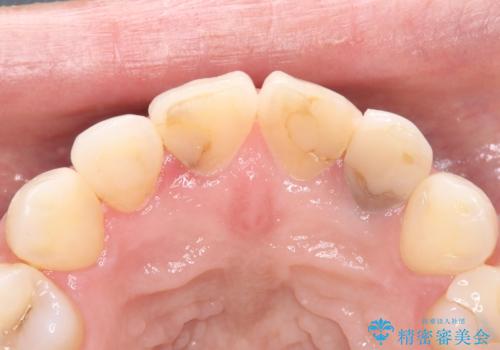

- 上顎の前歯4本が、過去の治療痕による変色や欠けで見た目が気になるとの主訴でご来院されました。患者様は、思い切り笑えるよう自然で美しい前歯を求めていらっしゃいました。そこで、最も天然歯に近い審美性を再現できるオールセラミッククラウンを用いた治療計画を立案しました。歯並びや色のバランスを整え、長期的に安定する美しい口元を獲得することを目指します。

治療はまず、審美性を最大限に高めるために、歯肉のラインや前歯の形を整えることから始めました。その後、4本の歯を丁寧に形成し、金属を一切使用しないオールセラミッククラウンを作製しました。